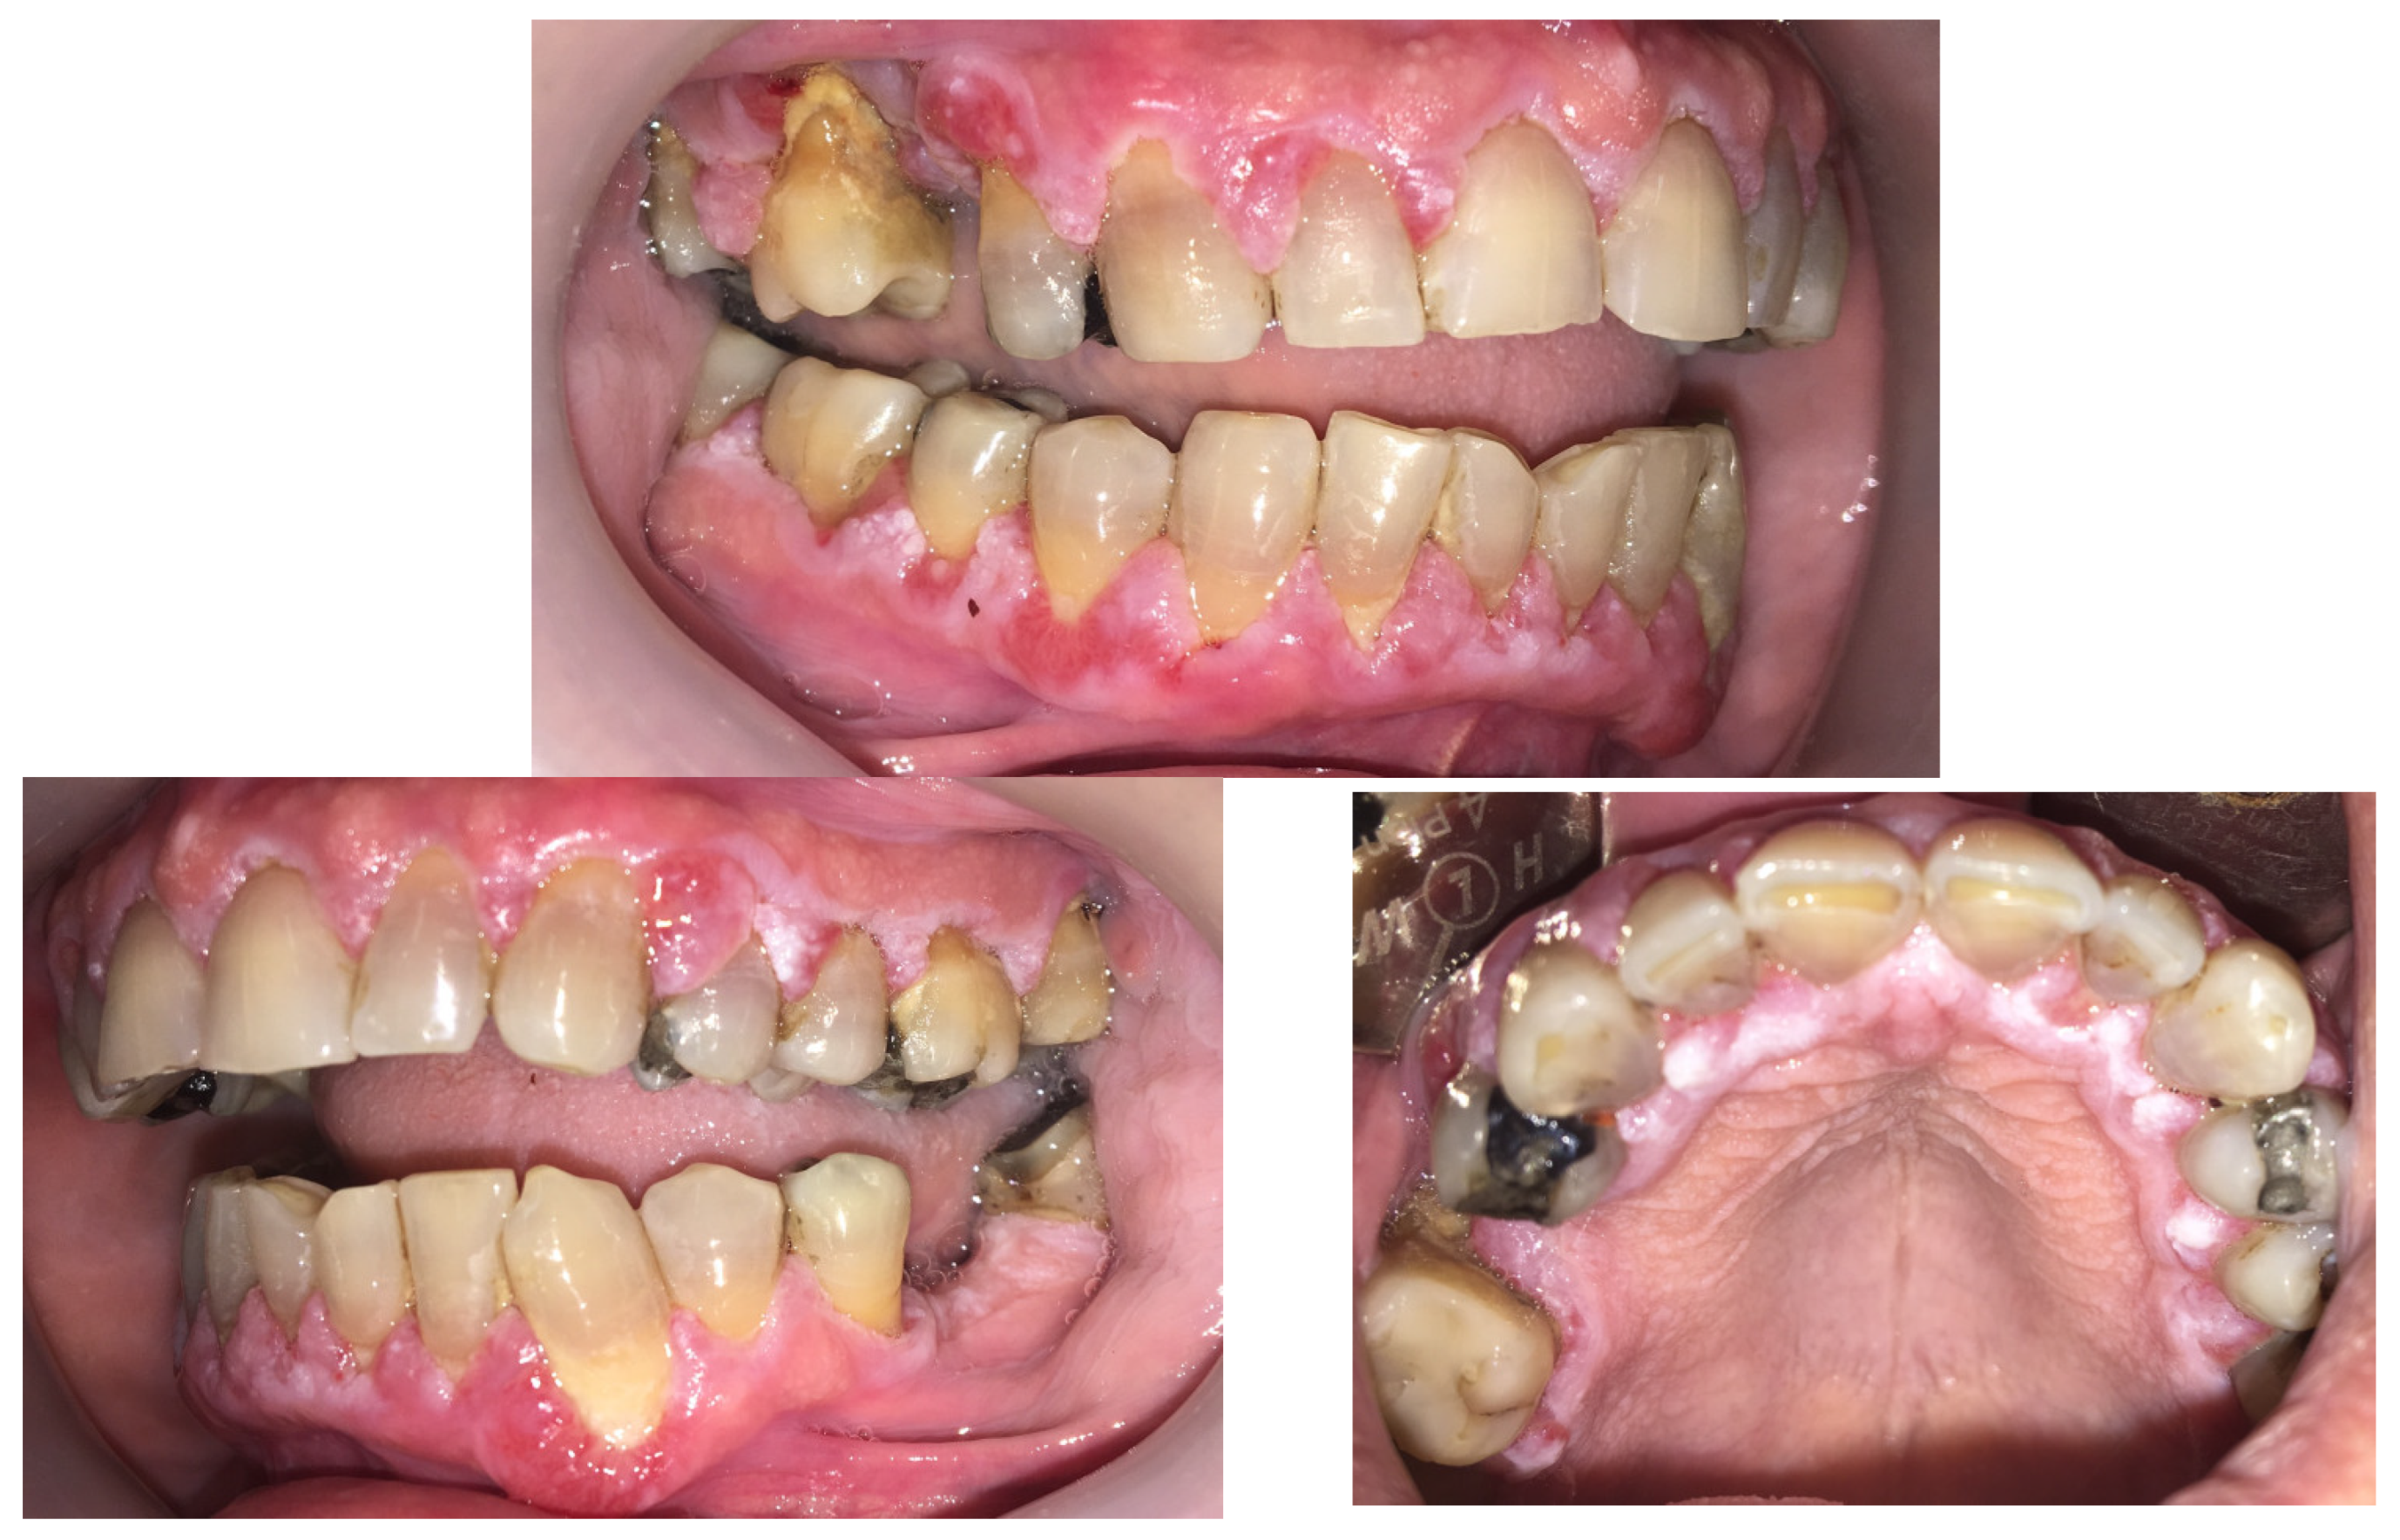

2. Case Presentation